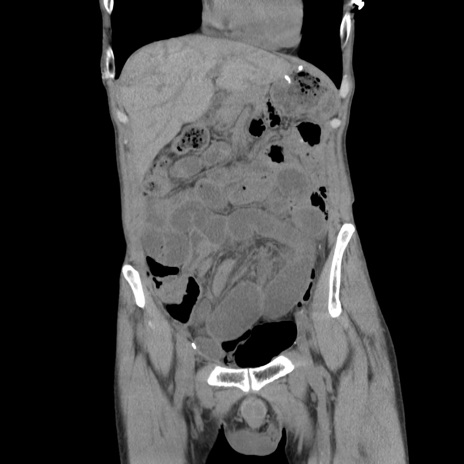

症例11(冠状断像)

【症例】 60歳代男性

【主訴】 下腹部痛

【現病歴】 本日夜中より下腹部痛の症状認め、受診。

【既往歴】 膀胱癌(膀胱全摘+尿管皮膚瘻術) 、胃癌術後

【身体所見】 BT 35.3℃、PR 58/min、BP 136/98mHg、腹部平坦、軟、腸蠕動音±、ストマ留置あり、左上腹部~正中部に圧痛あり、反跳痛なし。

【データ】WBC 5100、CRP0.01